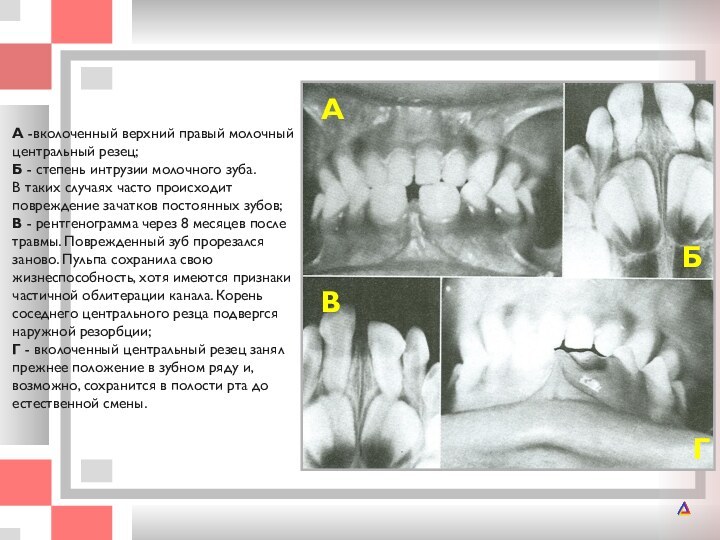

А -вколоченный верхний правый молочный центральный резец; Б - степень интрузии

степень интрузии молочного зуба. В таких случаях часто происходит повреждение

зачатков постоянных зубов; В - рентгенограмма через 8 месяцев после травмы. Поврежденный зуб прорезался заново. Пульпа сохранила свою жизнеспособность, хотя имеются признаки частичной облитерации канала. Корень соседнего центрального резца подвергся наружной резорбции; Г - вколоченный центральный резец занял прежнее положение в зубном ряду и, возможно, сохранится в полости рта до естественной смены.

Г